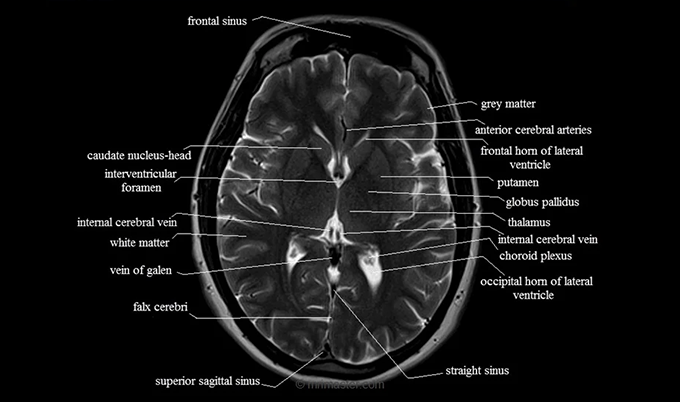

Normal Brain MRI Images and Anatomy

When radiologists describe what a healthy brain MRI looks like, they're reviewing multiple anatomical structures across several imaging planes. Each structure has a predictable, normal appearance - and recognizing that pattern is exactly what board-certified radiologists are trained to do.

Gray matter vs white matter

The brain's two primary tissue types produce distinct signals on MRI. Understanding this difference helps decode your report language.

Gray matter consists primarily of nerve cell bodies - the neurons that process information. On T1-weighted images, gray matter appears slightly darker than white matter. It forms the cerebral cortex along the brain's outer surface, and also makes up deep structures including the basal ganglia, thalamus, and hippocampi. In a healthy brain MRI, gray matter shows consistent thickness across the cortex with no focal areas of thinning or abnormal signal.

White matter consists of myelinated nerve fibers that carry signals between brain regions - the brain's internal communication infrastructure. It appears lighter than gray matter on T1 sequences. A normal brain MRI shows white matter with uniform signal intensity and a clear, predictable distribution. When white matter shows small areas of increased signal on T2 or FLAIR sequences - called white matter hyperintensities - the significance depends heavily on age, number, location, and pattern.

- Axial (transverse) view - Horizontal cross-sections from top to bottom, like slices through a loaf of bread. This is the view most people recognize from medical imaging on television. Axial slices clearly show the cerebral hemispheres, lateral ventricles, basal ganglia, and thalami. Most white matter assessment happens on axial views.